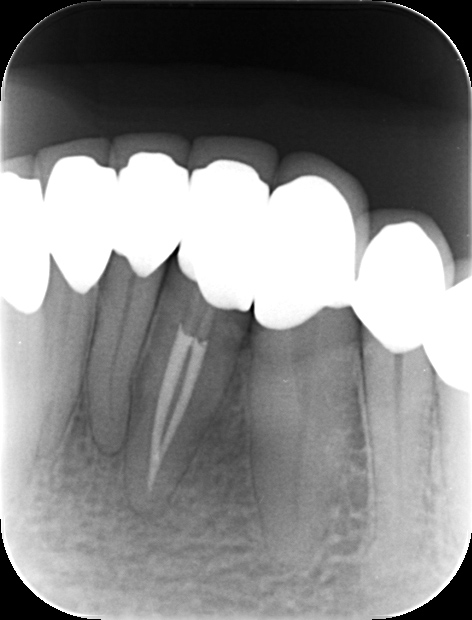

根管は歯の内部に位置しているため、肉眼では確認できません。狭く複雑な根管の形状を把握するためには、X線検査が必要です。

X線検査といえば、よく使われるのは「レントゲン」ですが、当院では「CT」を採用しています。CTは、お口の周りを360度回転しながら撮影するので、立体的で鮮明な画像が得られます。

次の画像は、同じ歯をCTとレントゲンで撮影したものの比較です。

左がCT、右がレントゲンとなります。

CT画像(左)では黒い影が見えますが、レントゲン画像(右)にはその影がありません。この黒い影は、歯の根の炎症です。つまり、レントゲンだけで検査していたら、この炎症は見逃されてしまうということです。

CTを使用することで、初期の炎症も見逃すことなく、適切な診断が可能になります。